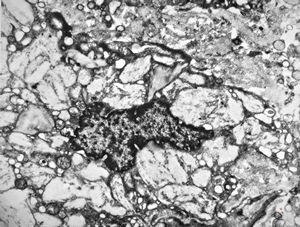

M,54y. | Whipple disease

Whipple disease